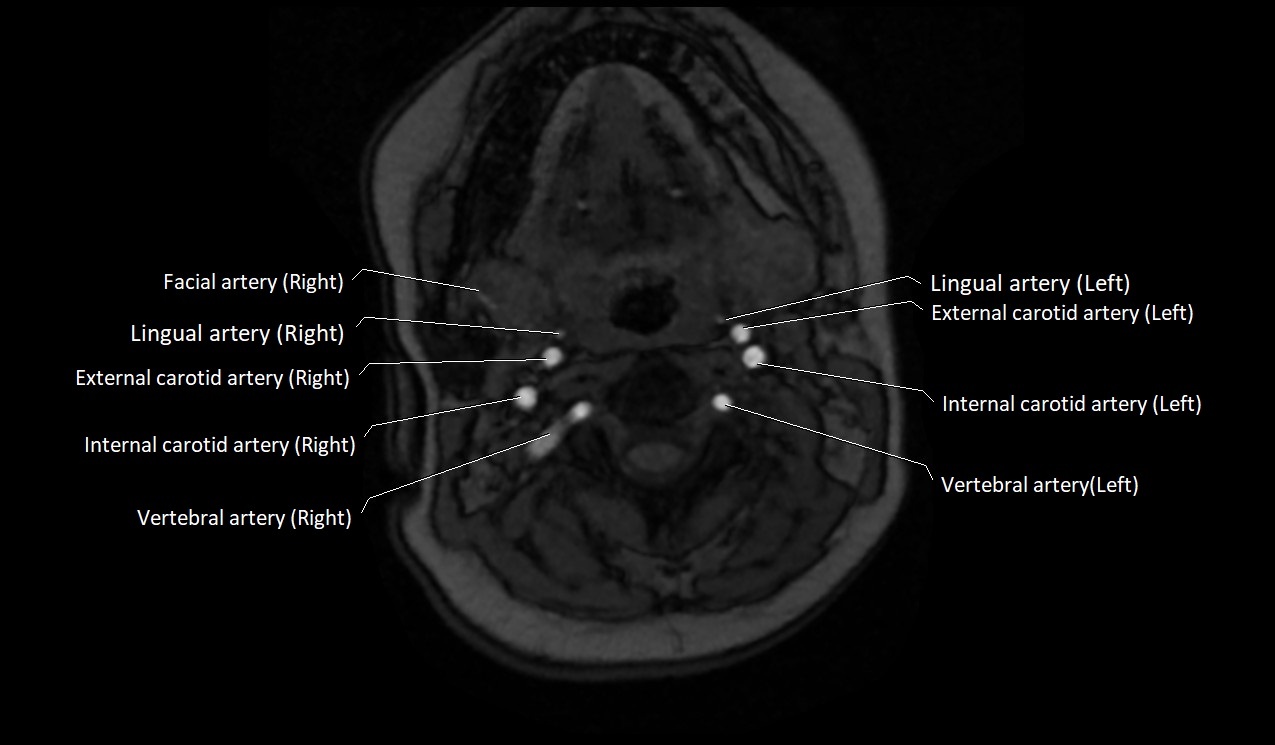

MRI Appearance:

• T1-Weighted Images:

• Appears as a tubular, hypointense (dark) structure relative to muscle

• May show flow void if the blood flow is fast

• T2-Weighted Images:

• Typically hypointense or isointense to muscle, but can be hyperintense if slow flow or stasis is present

MRI images